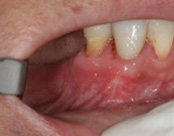

This patient presented with a failed root canal. The root canal became infected. An apicoectomy (apical microsurgery) was performed using the laser. Patient had minimal swelling, minimal discomfort, and fast healing. The tooth was saved and an implant avoided. This tooth tends to have a lower success rate with root canal therapy; thankfully apical microsurgery was available to save the tooth.

At the 3 month follow-up, the gums look like nothing was done thanks to the skill and use of the laser for the procedure.